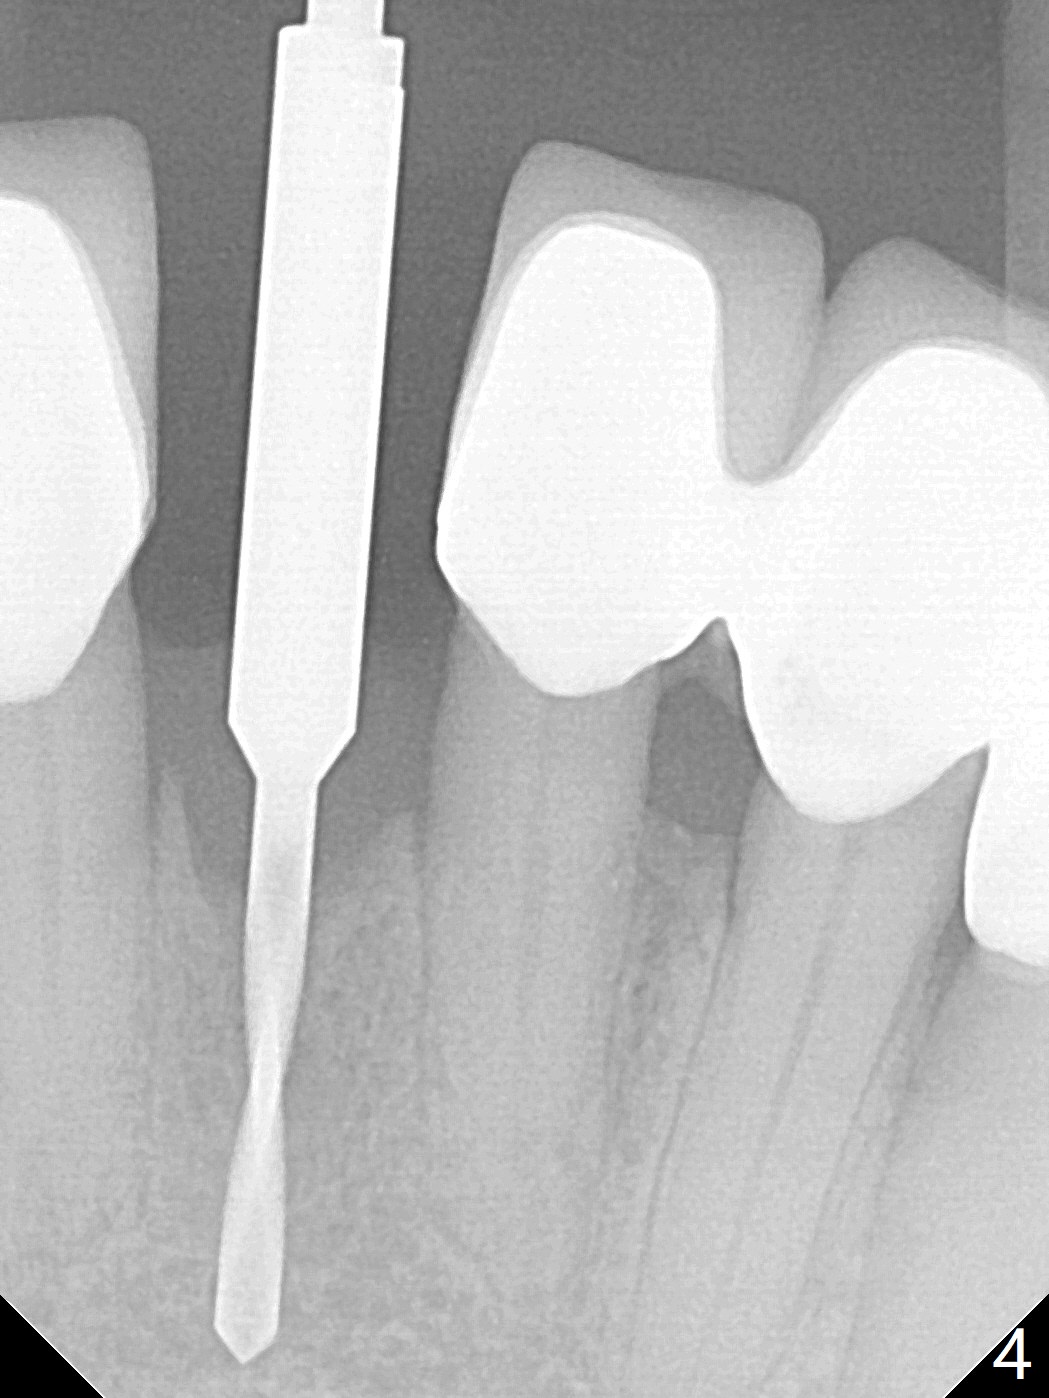

种植前与66岁女病人再次讨论下前牙正中种植可能产生不对称问题,她好像不在乎。术前检查显示下前牙正中间隙偏左(图一),处理似乎容易,但是牙槽嵴相当狭窄(图一 *,二 箭头)。牙槽嵴切除后(大约3 毫米宽(颊舌侧)),初期钻洞似乎偏移右边(图三),矫正后(图四),植入2乘10(4)毫米连体植体(图五,比预计小,因为骨质薄),放置骨粉(图五,六 *)和膜,缝合,制作即刻修复物(图七 T),病人满意,牙槽骨饱满了。术后一个多月临时牙冠取出修正,伤口愈合,由于植骨颊侧没有凹陷(图八),而舌侧隆起(图九:*,与图二术前对比)。其实病人不小心吃牛肉时损伤植体,疼痛几天。尽管最近吃饭时植牙又受伤,但是没有松动,也没有骨质吸收,就是局部结石多(图十,术后四个月)。正式牙冠术后4.5个月粘固(图十一)。